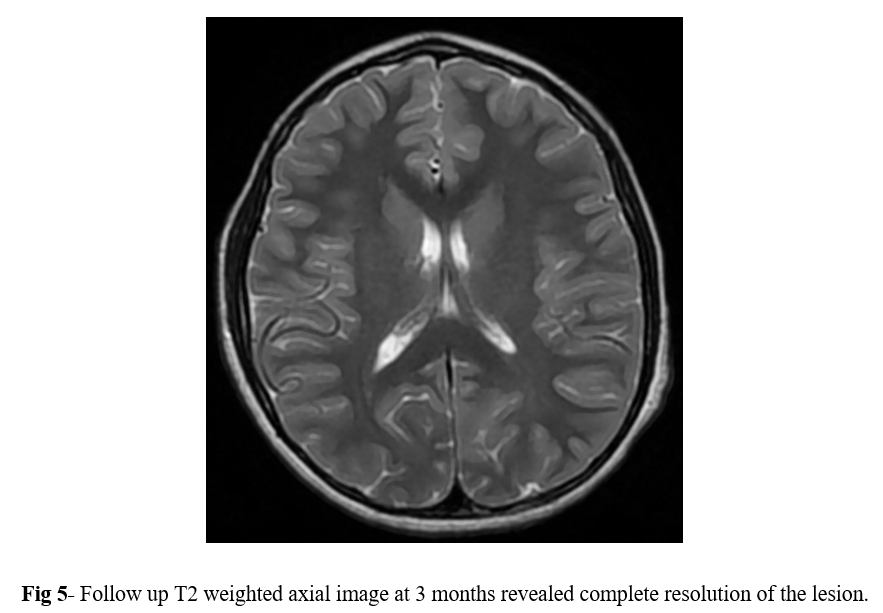

MRI of the brain with contrast was performed using 1.5 tesla scanner (GE Medical System). An oval well-circumscribed lesion was noted in the splenium of the corpus callosum in the midline (Figure 1). The lesion displayed restricted diffusion with low ADC values (Figures 2 and 3). No evidence of mass effect or perifocal edema was seen. No evidence of abnormal post-contrast enhancement was noted (Figure 4). No lesions are seen in the periventricular white matter and in the subcortical U fibers. In view of the clinical history and morphology of the lesion was read as reversible splenial lesion syndrome (RESLES). The differential diagnosis that were considered included ADEM, multiple sclerosis, encephalitis and glial tumor.

MRI follow-up at 3 months revealed complete resolution of the lesion. No evidence of restricted diffusion or abnormal post-contrast enhancement was observed on the follow-up scan (Figure 5). Evaluation of rest of the brain was unremarkable. The patient was no longer symptomatic for headache or staring episodes.